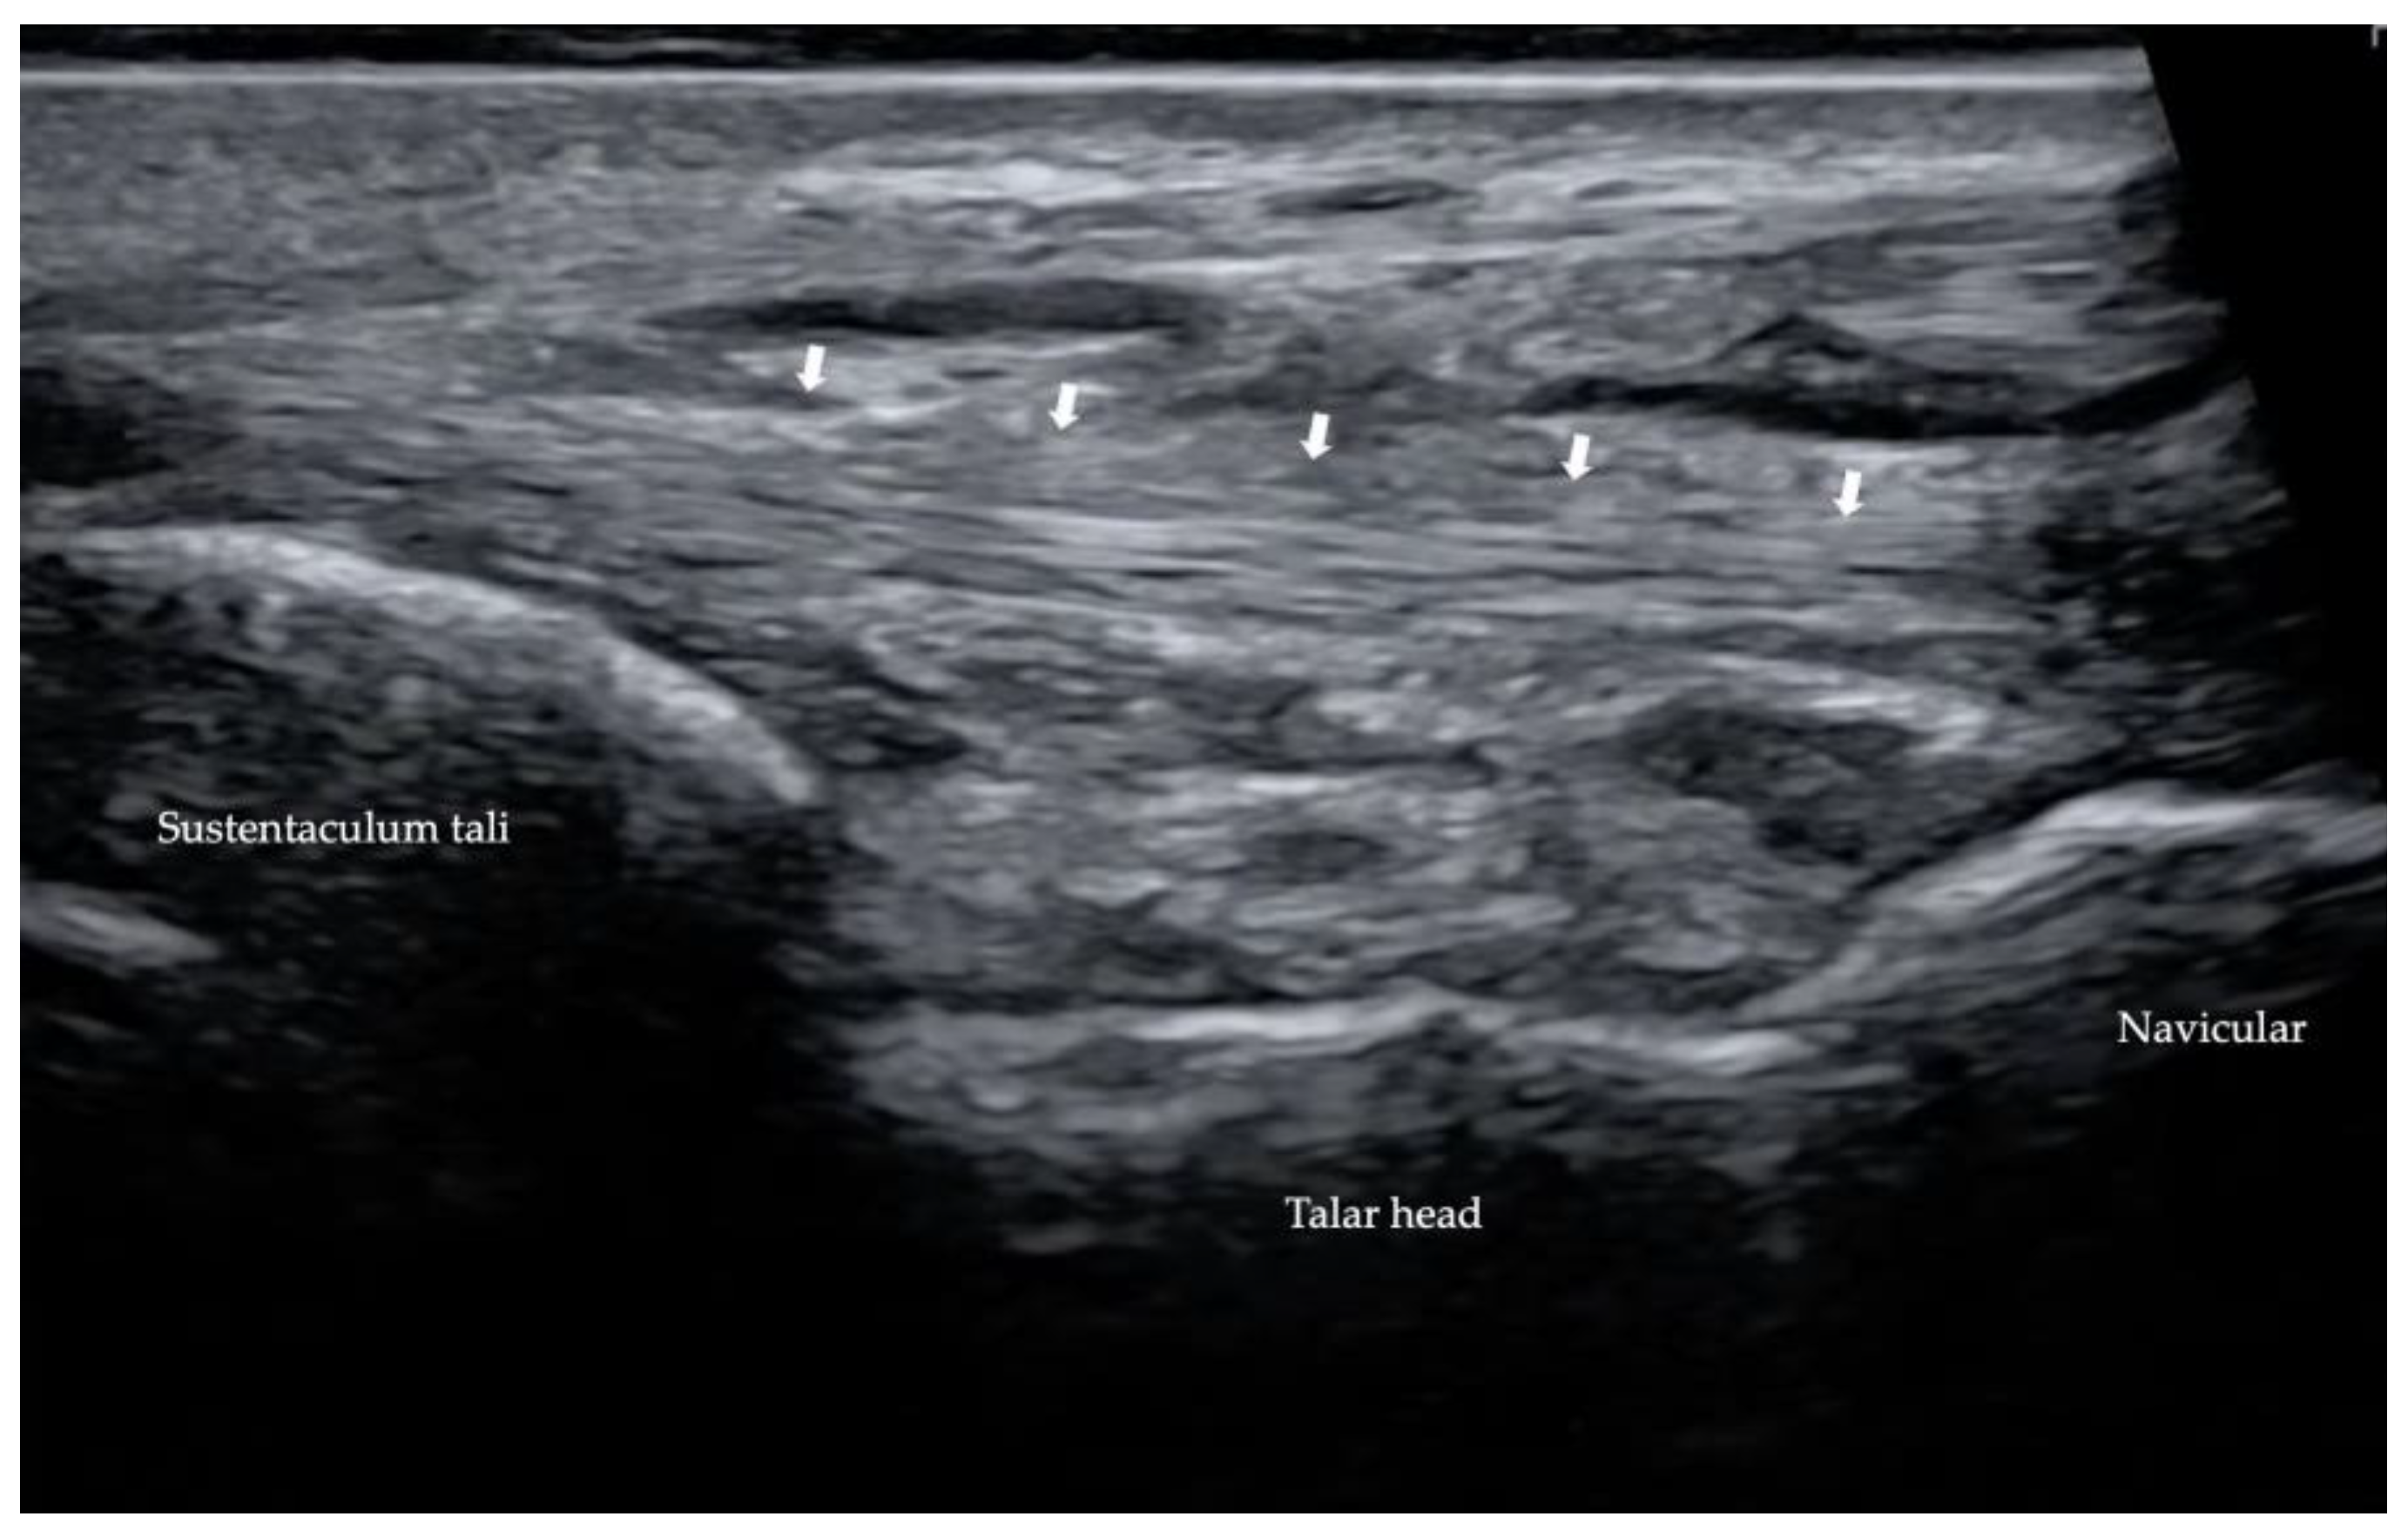

2.2.2. Spring Ligament

2.3. Ultrasound (US)